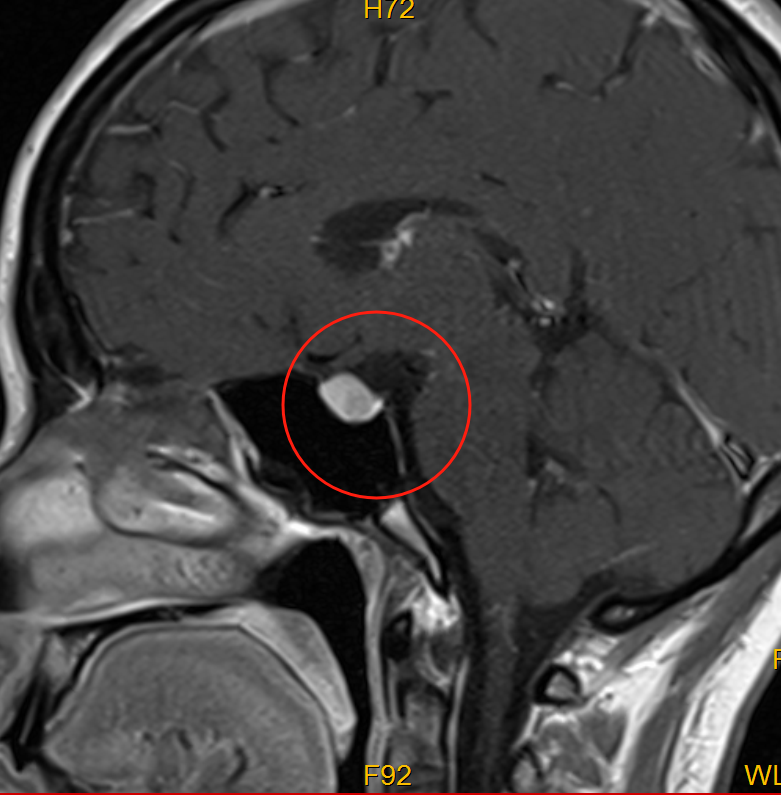

接诊医生详细询问病史后,安排了颅脑 MRI+增强检查,结果提示:林女士的头痛根源并非普通疲劳,而是垂体区域存在异常——考虑为 Rathke 囊肿、垂体神经内分泌肿瘤,且肿瘤已出现出血,正是这部分出血和肿瘤本身的压迫,直接引发了她日益加重的头痛。

神经外科主任林友城召集手术团队紧急讨论:由于肿瘤已出血并压迫周围组织,若不及时干预,头痛会持续加剧,还可能进一步损伤视力甚至影响内分泌功能。结合林女士年轻、对术后恢复和外观有较高需求的特点,团队最终确定采用「显微镜下经鼻蝶鞍区占位切除术」——这种手术最大的优势在于「微创不开脑」,无需在头部做任何切口,仅通过鼻腔这一自然通道就能直达鞍区病变部位,术后体表完全无疤痕,既能最大程度降低手术创伤,又能精准解决问题。